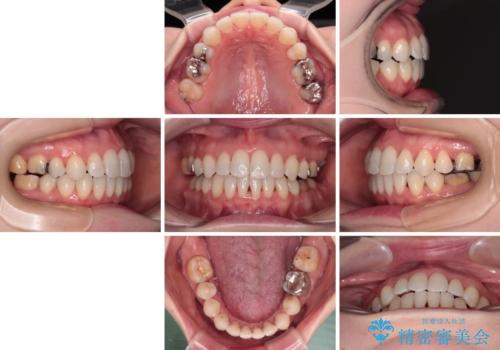

イレギュラーな大臼歯抜歯矯正であったため、治療期間の長期化が想定されましたが、何とか3年ちょうどで終えることができました。

今後は目立っている銀歯を中心にセラミッククラウンなどへ交換していく予定です。